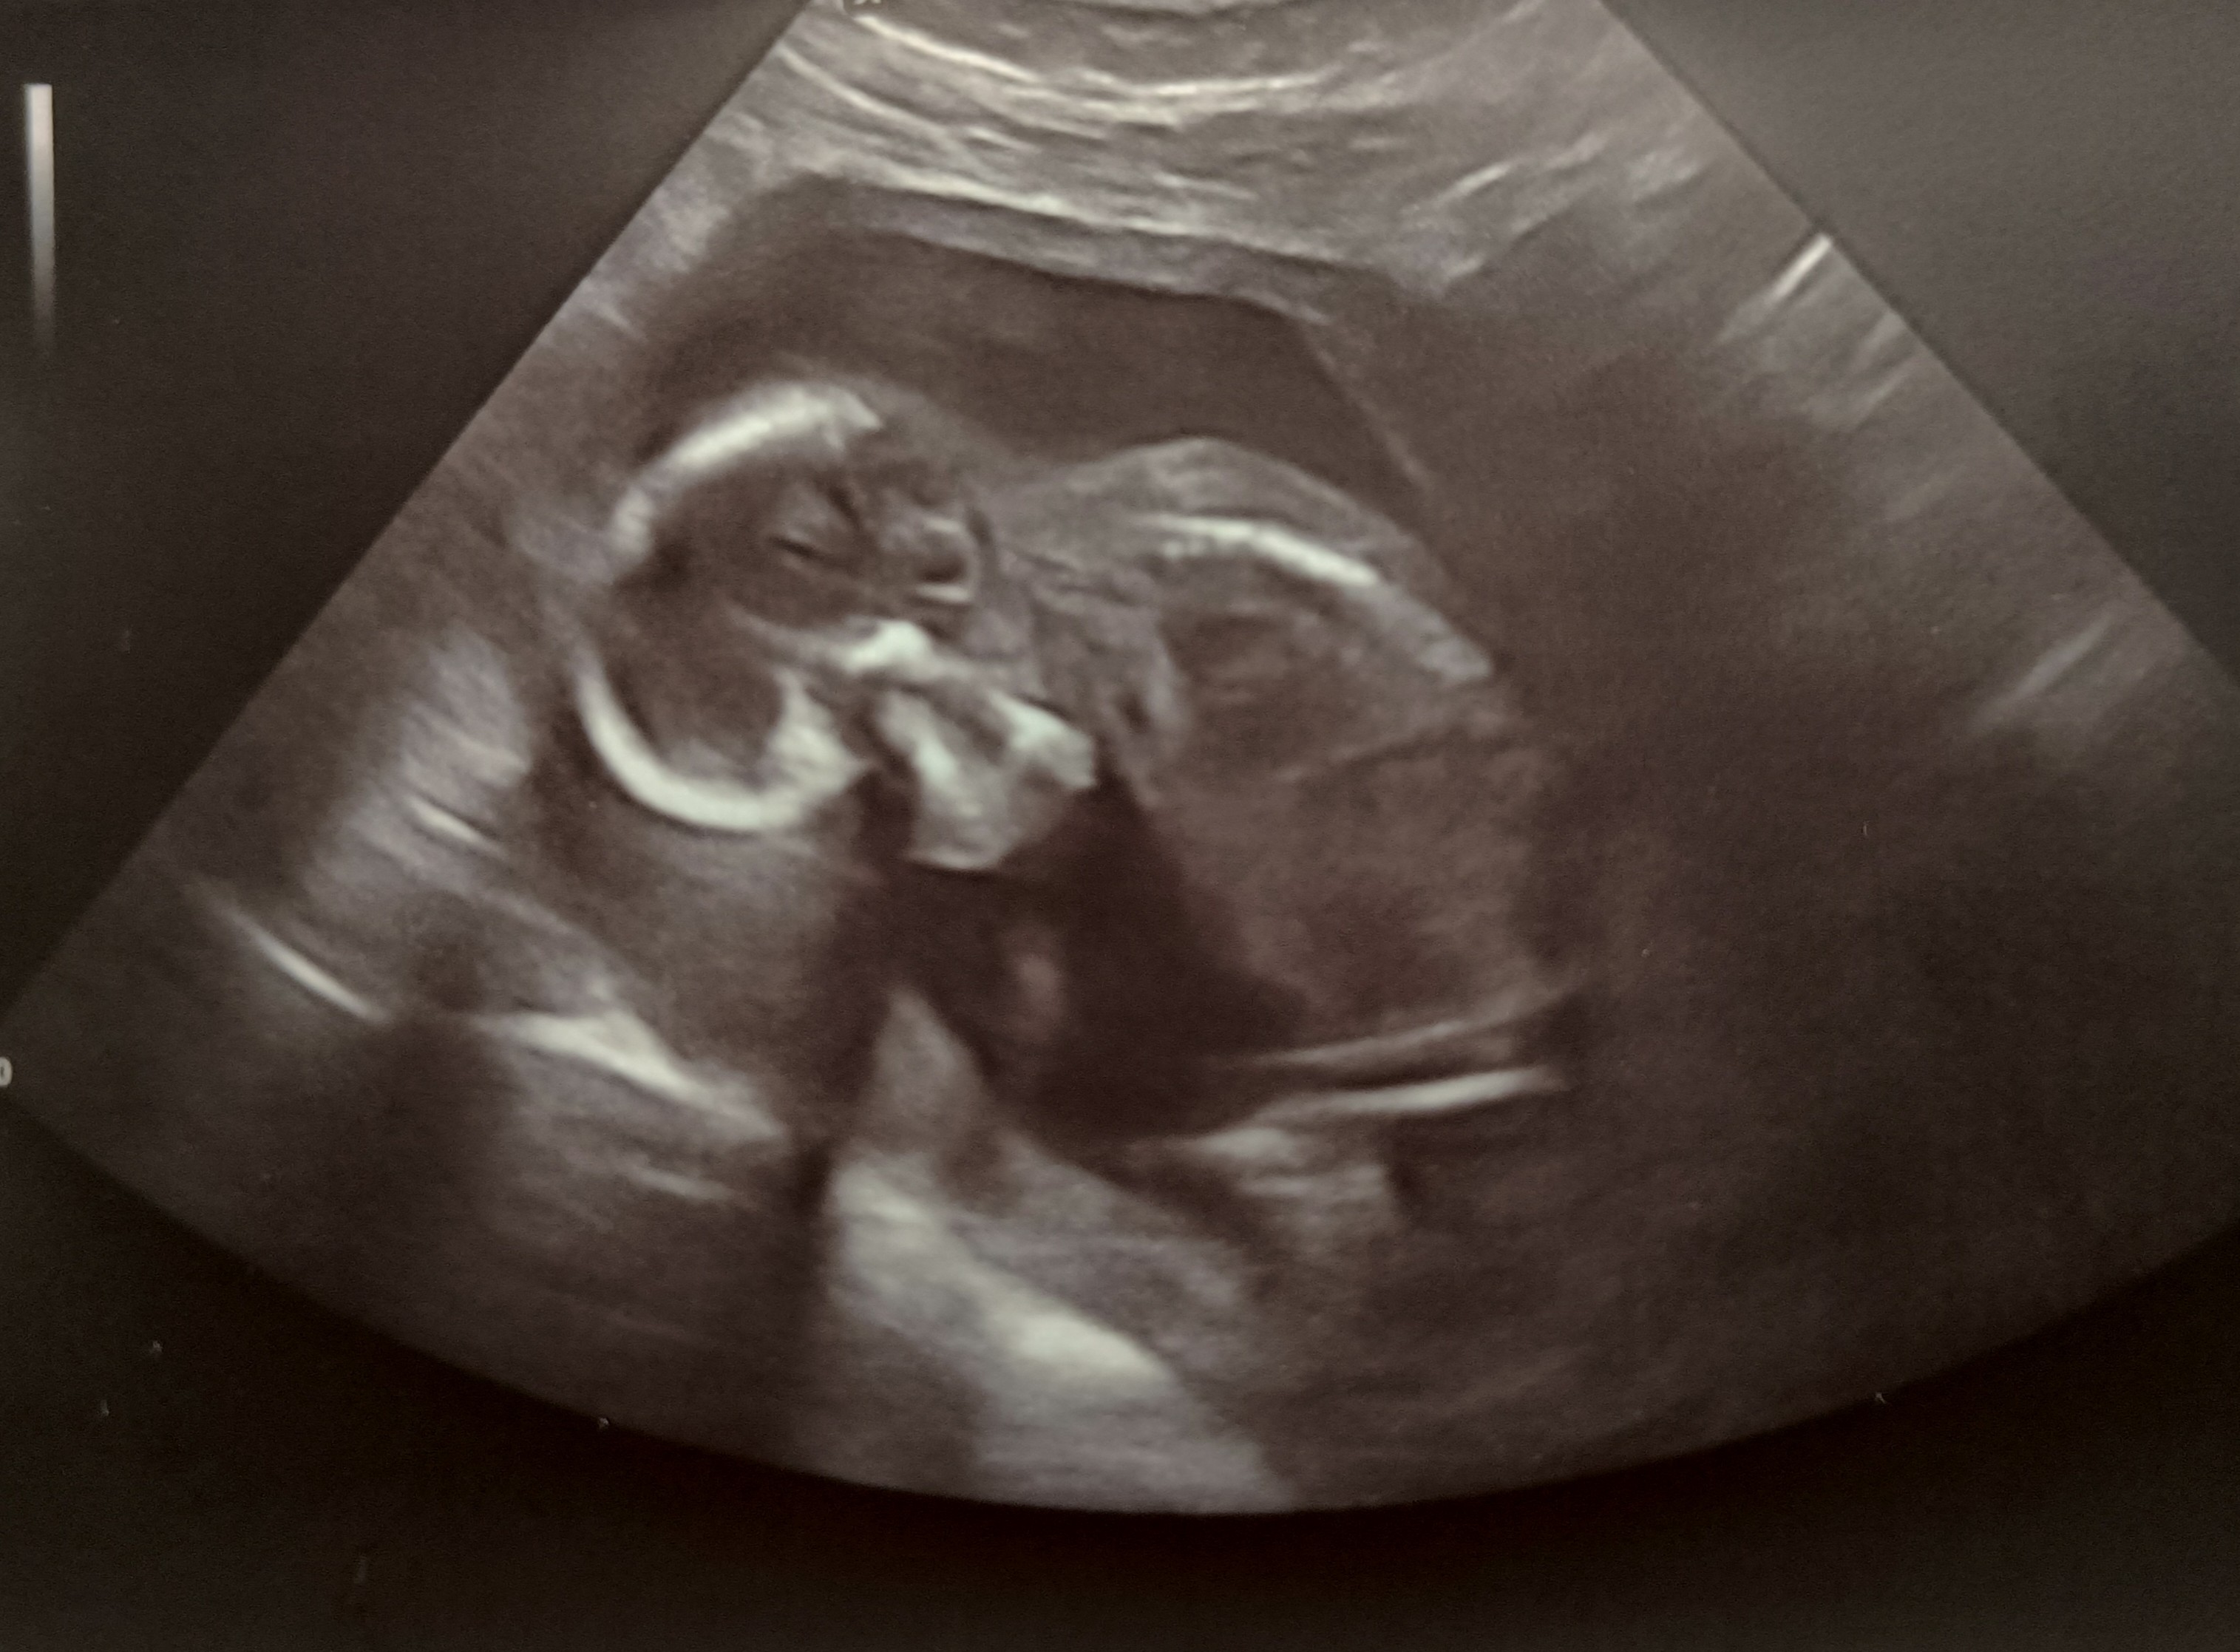

Hej. My już po wizycie, na 90% mamy córeczkę, waży 148gram 🩷 Jak ostatnio była aktywna wieczorem, tak wizytę przespała 😁

kolejna wizyta to połówkowe 29.09

Załączniki

• IMG_20230908_195357.jpg

IMG_20230908_195357.jpg

872,6 KB · Wyświetleń: 96